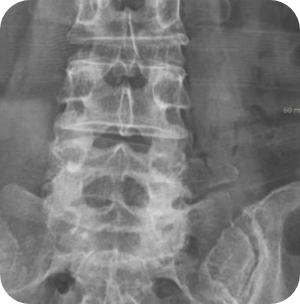

"걷다보면 다리가 저려서..도저히 못 걷겠다.", "시술도, 수술도 해봤지만..여전히 통증이 가시질 않는다." 허리에 발생하는 협착증 중 까다롭고 진단이 어려워 많은 환자들을 여러 병원으로 전전하게 만드는 대표적인 질환이 바로 극외층협착증입니다. 질환명마저도 생소한 이 질환은 안타깝게도 많은 의사들이 진단 자체가 어려운 경우도 있고, 진단을 하더라도 나사못고정술로만 치료할 수 있는 질환으로 잘못 인식하고 있습니다. 극외층협착증은 진단은 물론 치료도 까다로워, 내시경 수술로만 하기에는 치료 만족도가 높지 않은 질환입니다.

- 극외측협착증

- 척추분리증성 전방전위증